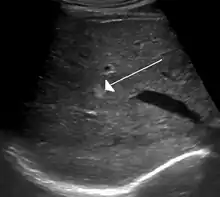

Ultrasound of hemangioma in the liver

Cavernous hemangiomas are erroneously called the most common benign tumors of the liver.[13] Usually one malformation exists, but multiple lesions can occur in the left or right lobe of the liver in 40% of patients.[3] Their sizes can range from a few millimeters to 20 centimetres. Those over 5 cm are often referred to as giant hemangiomas.[3] These lesions are better classified as venous malformations.

On ultrasound, cavernous haemangiomas in liver appeared as homogenous, hyperechoic lesions with posterior acoustic enhancement. On CT or MRI scans, it shows peripheral globular/nodular enhancement in the arterial phase, with portions of attenuation of enhancing areas. In the portal venous phase, it shows progressive centripetal enhancement. In delayed phase, it shows retention of contrast. It shows a high signal on T2 weighted images.[23]